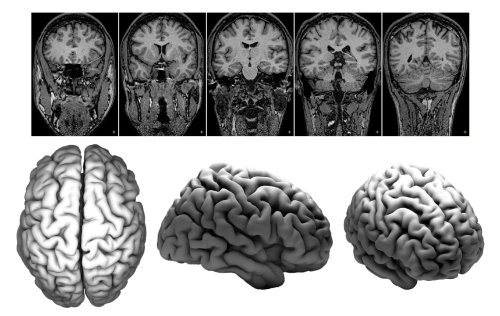

Development and evolution of brain folding and brain organisation

The mammalian brain is astonishingly diverse. Not only its size varies several orders of magnitude – from the 3 grams of the mouse brain to the 6 kg of the blue whale brain – but also its geometry and function. There is indeed a striking, largely unexplained, relationship between the folding of the mammalian brain and its cellular, functional and connective organisation. Brain folding appears as much more than a mere mechanical epiphenomenon, and besides its major evolutionary relevance, many psychiatric disorders such as autism or schizophrenia, are related to changes in brain folding.

I will present a brief overview of the developmental processes leading to the folding of the brain, and show some examples of functional correlates of brain folding in humans and other mammalian species. Finally, I will discuss some of the current theories proposed to explain the mechanism underlying the relationship between brain geometry and brain organisation, including our ongoing project on computational modelling and analysis of the development of the ferret brain.